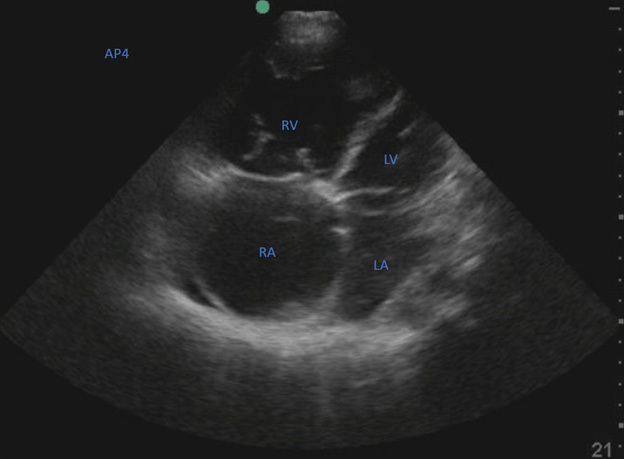

In addition to lower extremity ultrasound, cardiac ultrasound often is included in the evaluation of a suspected PE. The most frequently sought sign is that of right ventricle (RV) dilation, which has a sensitivity and specificity of 63.4% and 87.4%, respectively, for a PE. To assess dilation, ultrasound visualization compares the RV to the left ventricle (LV). If the RV/LV ratio is ≥ 1, it is suspicious for right ventricular dilation, as evidenced by Figure 2.37

Figure 2. Cardiac Ultrasound Suspicious for Right Ventricular Dilation |

![]() |

Courtesy of Jimmy Truong, DO. |

Other cardiac ultrasound modalities that are not used as frequently as RV dilation had similar sensitivities and specificities. One of these other findings is that of the D-sign, where the flattening of the interventricular septum causes the left ventricle to appear in the shape of the letter “D.” This sign is indicative of right ventricular volume overload causing an increased pressure and can be seen best using a parasternal short axis view. Along with some other secondary signs of right heart strain, echocardiography has the benefit of directly viewing the right side of the heart and can evaluate both right ventricular function as well as potentially identify any intracardiac thrombi.4 A visible RV thrombus is present in approximately one in 20 patients with PE, and a past meta-analysis showed 100% specificity among five different studies.37